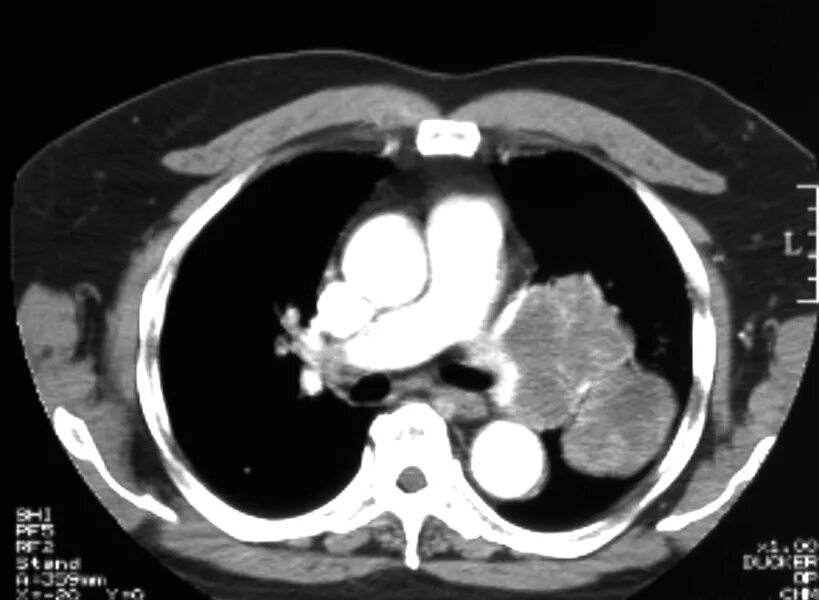

Метастазы в средостении легких